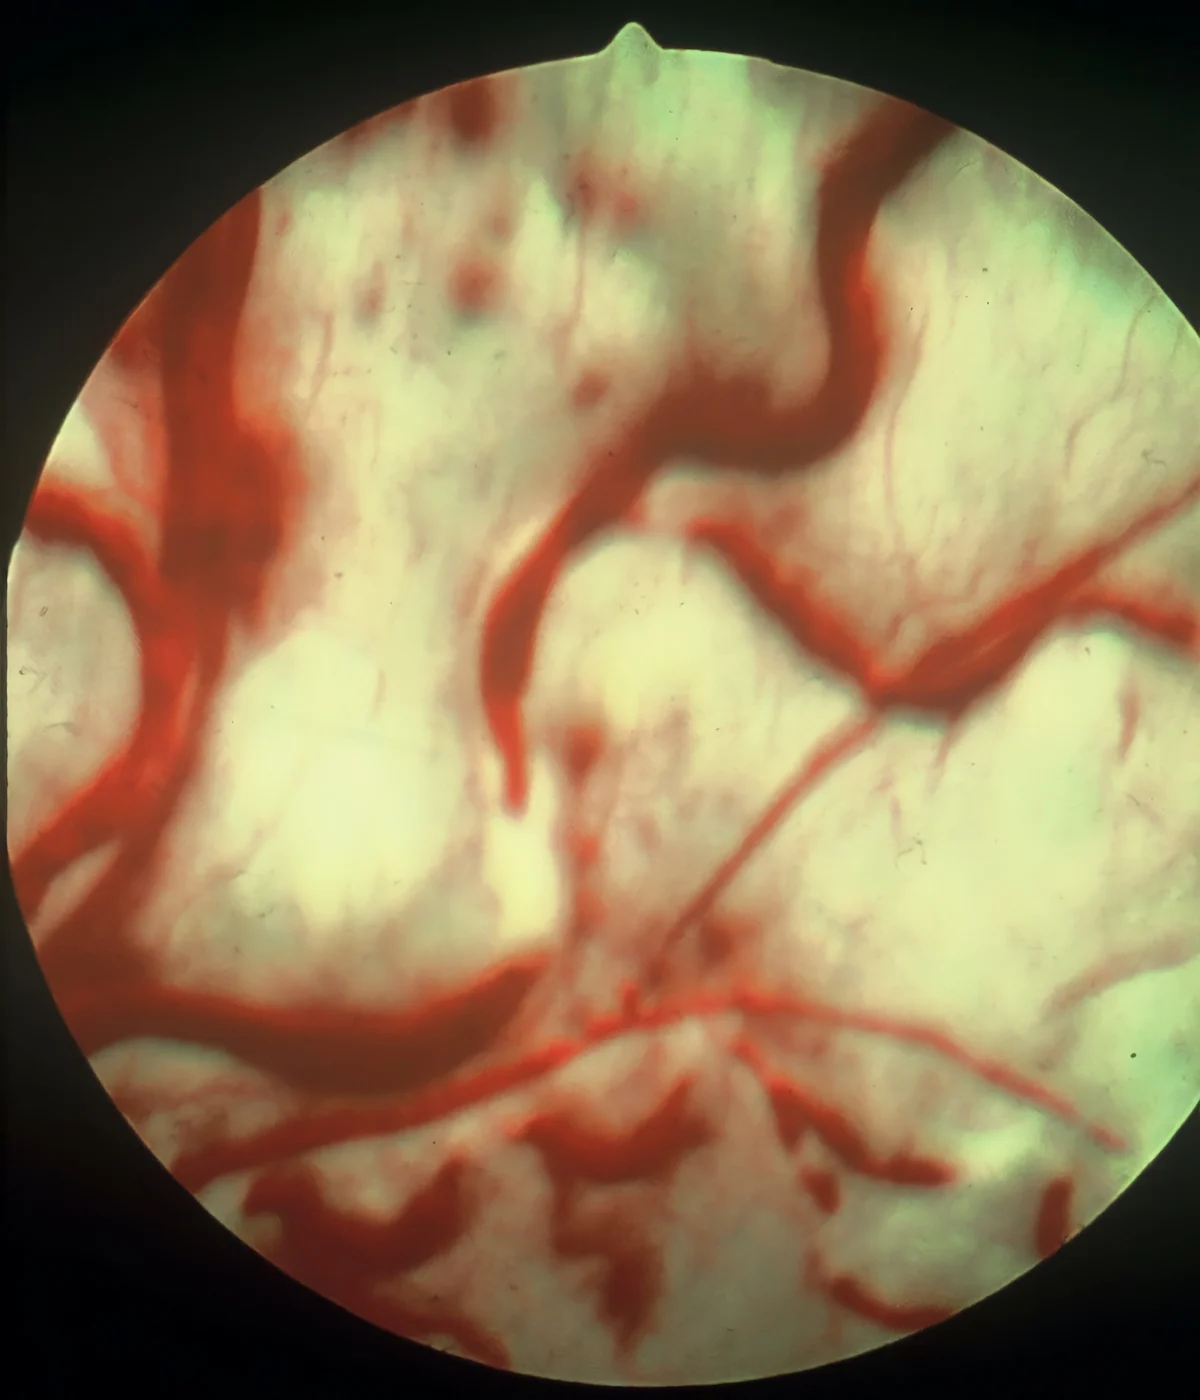

Retinal image with thick winding red vessels seen within bright yellow retina.

FIGURE 9

Tortuous course of retinal vasculature due to hypertension in a dog

Vascular tortuosity refers to abnormal twists and turns (often at acute angles; different from the natural arborizing branching pattern of retinal vasculature) related to mechanical forces associated with hypertension that affect wall rigidity, blood pressure, blood flow, axial tension, and wall structural changes (Figure 9).15 Retinal edema may appear via indirect ophthalmoscopy as areas of the tapetum that are gray, are indistinct, have altered reflectivity, or have pale yellow or patchy irregularities compared with the surrounding tapetum (Figure 10).